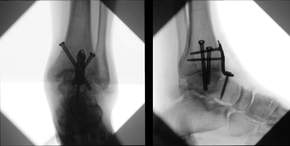

Unser Team aus Ärzten, Pflegekräften, Therapeuten und Orthopädietechnikern arbeitet gemeinsam, um für Sie individuelle Behandlungspläne zu entwickeln, die auf Ihre persönlichen Bedürfnisse zugeschnitten sind. Wir nutzen modernste Technologien, minimalinvasive und arthroskopische Verfahren, um Ihre Gesundheit und Ihr Wohlbefinden wieder herzustellen und Sie zurück in die Bewegung zu bringen. So können komplizierte Gelenkeingriffe und Bruchversorgungen z.B. mit intraoperativer 3D-Bildgebung durchgeführt werden.

- gesamtes Spektrum der Frakturversorgung